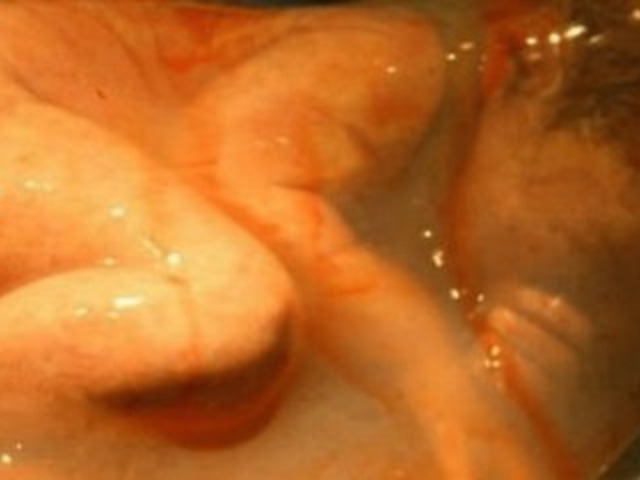

Vídeos divulgados nas redes sociais em 11 e 12 de dezembro exibiram, respectivamente, os bebês Miguel e Elis nascerem cobertos com a película amniótica, em imagens que aparentam uma certa estranheza para quem nunca teve acesso a registros reais sobre a ocorrência. Porém, apesar de o fato ser classificado como um feito raro e difícil de programar, não chega a ser um evento anormal ou prejudicial para a mãe ou criança, já que o bebê continua ligado à genitora pela placenta e permanece respirando normalmente.

(Fonte: g1 / Reprodução)